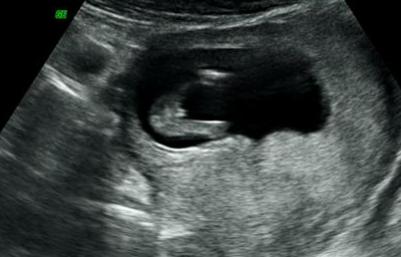

Hi we went for our 3D scan yesterday at 12w1d. Tech says its a girl, do you agree?